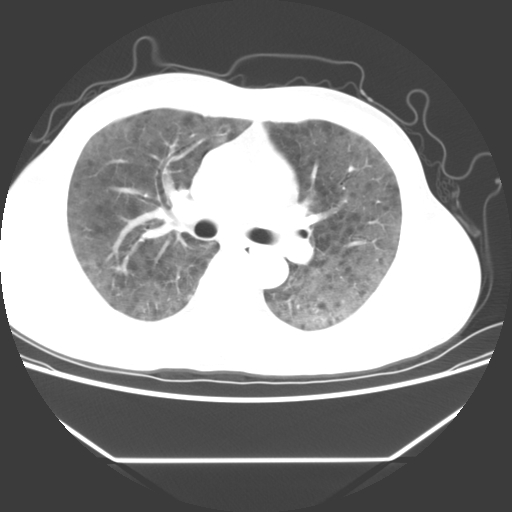

病人55岁,咳嗽,胸闷

忘了传病史了,病人55岁,咳嗽,胸闷

两肺部呈“毛玻璃”状改变,原因待查考虑感染性病变

病人是否发烧,两肺“磨玻璃”影,其间见空气支气管征和碎路石征。考虑肺泡蛋白沉着症。

两肺广泛对称磨玻璃样影,密度不均,考虑机遇性肺部感染。

双肺弥漫磨玻璃样病变,病史很重要。有感冒或发烧史,甲流不除外。无发烧可考虑肺泡蛋白沉积,但肺泡蛋白沉积边缘往往较清晰,与正常肺组织分界清晰

两肺弥漫间质性病变,考虑肺泡蛋白沉着症。建议进一步检查。

两肺“磨玻璃”影,其间见空气支气管征和碎路石征。考虑肺泡蛋白沉着症。